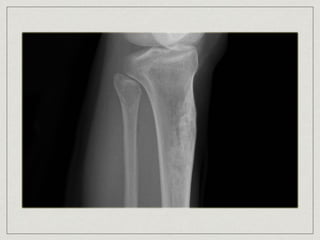

Chondrosarcoma

most common primary chest wall bone neoplasm

60% arises in costochondral arches or sternum

lobulated mass arising in medullary portion with

destruction of cortex and mineralization of tumor

matrix(mottled type of calcification)

treatment is complete resection, 5-yr survival of 64%

Chondrosarcoma most common primarychest wall bone neoplasm 60% arises in costochondral arches or sternum 30-40 years old cause is unknown slow enlarging mass become painful lobulated mass arising in medullary portion with destruction of cortex and mineralization of tumor matrix(mottled type of calcification) treatment is complete resection, 5-yr survival of 64%